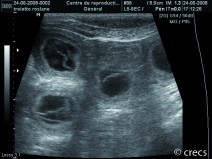

• Soirée La gestation : confirmation, suivi, prédiction de la mise bas et anticipation des risques

Emmanuel Topie (Dipl. ECAR, GERES), fort de son expérience universitaire et libérale, viendra vous présenter les dernières recommandations en matière de reproduction. Il abordera le suivi de la gestation chez la chienne et la chatte, depuis la...